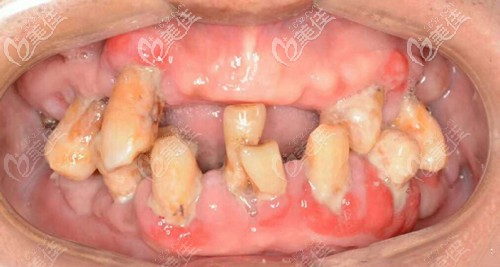

做种植牙前牙齿缺失、牙齿松动、牙周病较厉害

邱医生说我姥爷的口腔卫生状况不太好,牙周石比较厉害,牙齿缺失,虽然现在口内还10颗牙齿,也开始出现了松动的迹象,陆续的牙齿都会脱落,没有其他方案可以选择了。